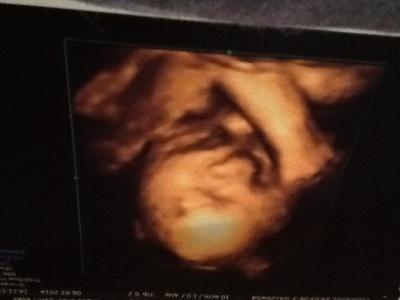

Hallo an Alle ::)) Wir waren heute beim 3 D Ultaschall und haben eine Zuckersüßes Foto bekommen :) Ich bin soooo verliebt. Auch mein Mann konnte es gar nicht glauben wie unser kleine Mann schon aussieht, er ist nun 35cm und ca. 1000g schwer

Bild zu Freude :) - Forum für Juni - Mamis

Oje Bild ist Falsch herum :(

Wirklich tolles Bild !!! Das Problem mit den Bildern hab ich auch oft. Egal, machen wir Kopfstand ;-) Lg